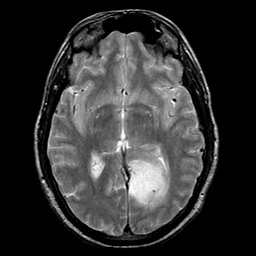

glioma overlay -- Slice #13

[Home][Help][Clinical] Slice 13